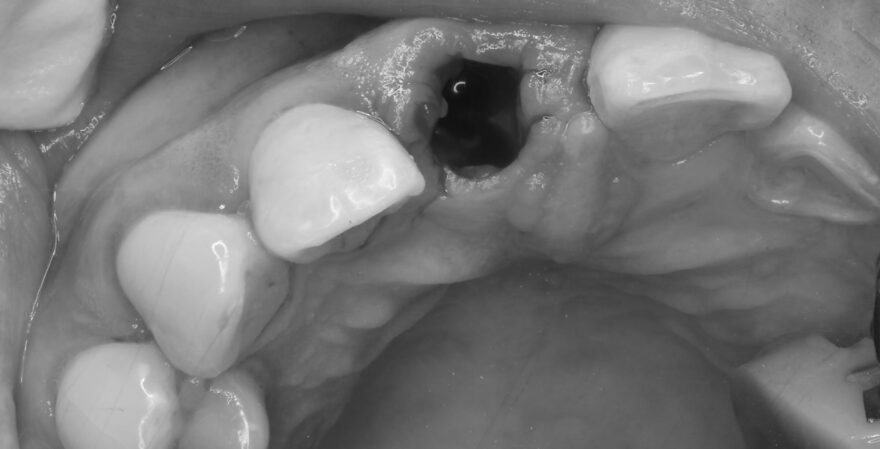

初診時口腔内写真

左側の差し歯が壊れてしまい、当院を受診されました。

歯根はとても小さく、顕微鏡治療でも残せないと判断しました。